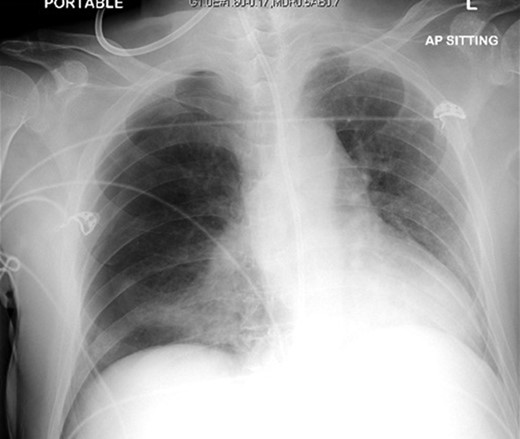

The patient was urgently reviewed by the cardiothoracic surgeons, and a small-bore chest tube was inserted, following which a computed tomography of the thorax was performed. This showed a residual but smaller pneumothorax with the chest tube in situ, associated with a small hemothorax (Fig. 3). Due to failure of conservative management and concern of a bronchopleural fistula resulting in air leak, he underwent explorative thoracoscopic surgery. Intraoperatively, an area of lung was noted with contusional changes and a bleb (Fig. 4), and a wedge resection of the right lower lobe was performed (Fig. 5). He made an uneventful recovery and was discharged.

Video assisted thoracoscopic surgery showing an area of right lung associated with a bleb and contusional changes.